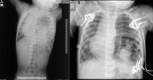

Chest X-ray (A) at presentation and (B) after ventilation.